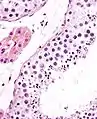

Seminiferous tubule (right) with sperm (black, tiny, ovoid). H&E stain.